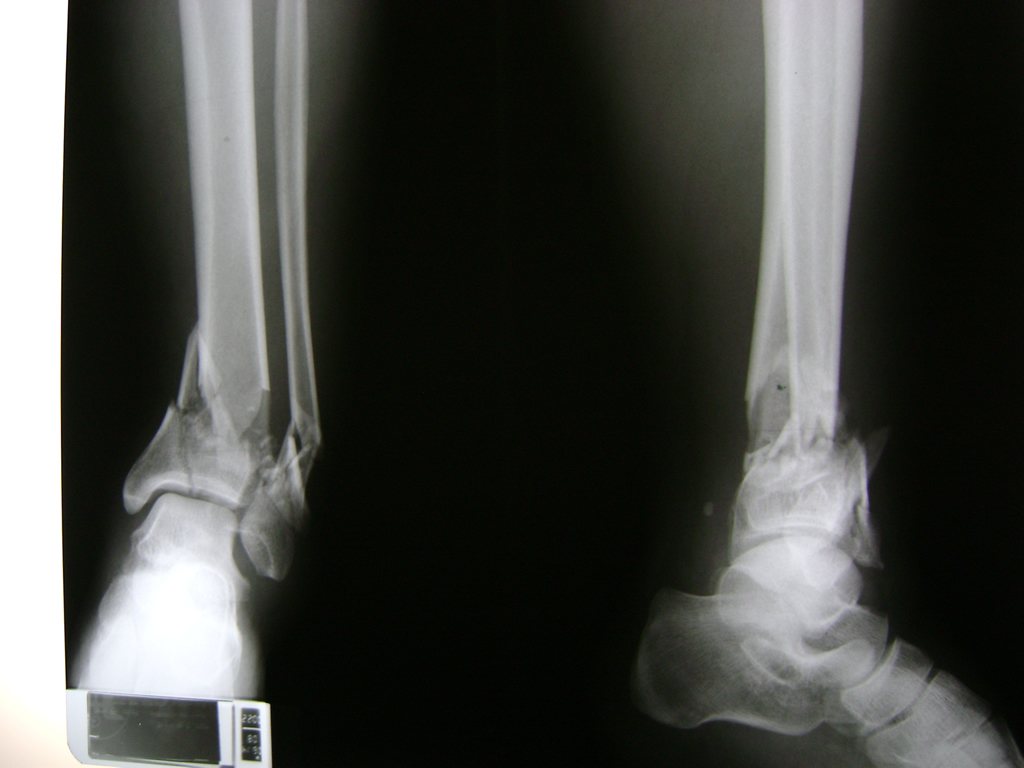

Una fractura de tobillo es la rotura de uno o más de los huesos del tobillo. Estas fracturas pueden ser:

- Los extremos de los huesos están desalineados entre sí (desplazados).

- La fractura se extiende hasta la articulación del tobillo (fractura intra-articular).